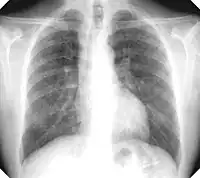

Fibrothorax and pleural effusion caused by silicosis